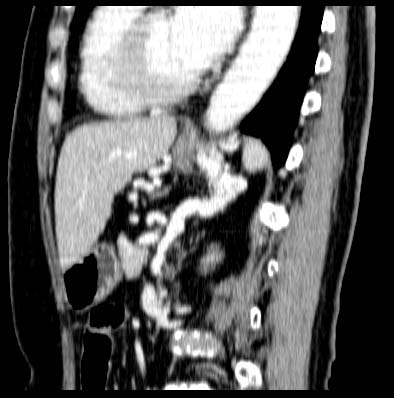

Gastric varix

Sagittal MPR